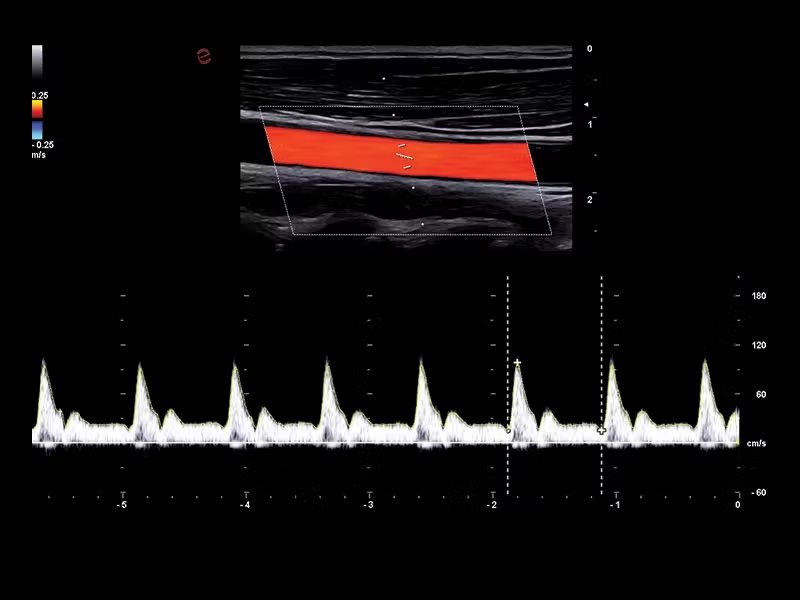

S MyLab™ A50 získáváte možnost provádět široké spektrum vyšetření, včetně jater, srdce, gynekologie a porodnictví, cév, prsu, štítné žlázy, muskuloskeletálního systému, urologie a pediatrie.